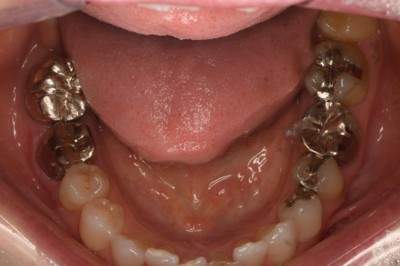

2022.2.5 抜歯後の消毒

口腔内写真

CT画像

骨の状態はそこまで悪くないが、欠損が大きい。

2022.3.12 抜歯1ヶ月後・移植

移植オペ

抜歯をして1ヶ月後、歯ぐきが治ってから、移植をおこなった。

移植時は動揺が大きいため、隣の歯にワイヤーで固定した。

2022.4.16 根管充填

移植2週間後から根管治療開始

次の回(翌週)で根管充填

2022.5 仮歯装着

根管治療後は仮歯をいれて経過をみていきました。

日に日に動揺がなくなっていくのがわかりました。